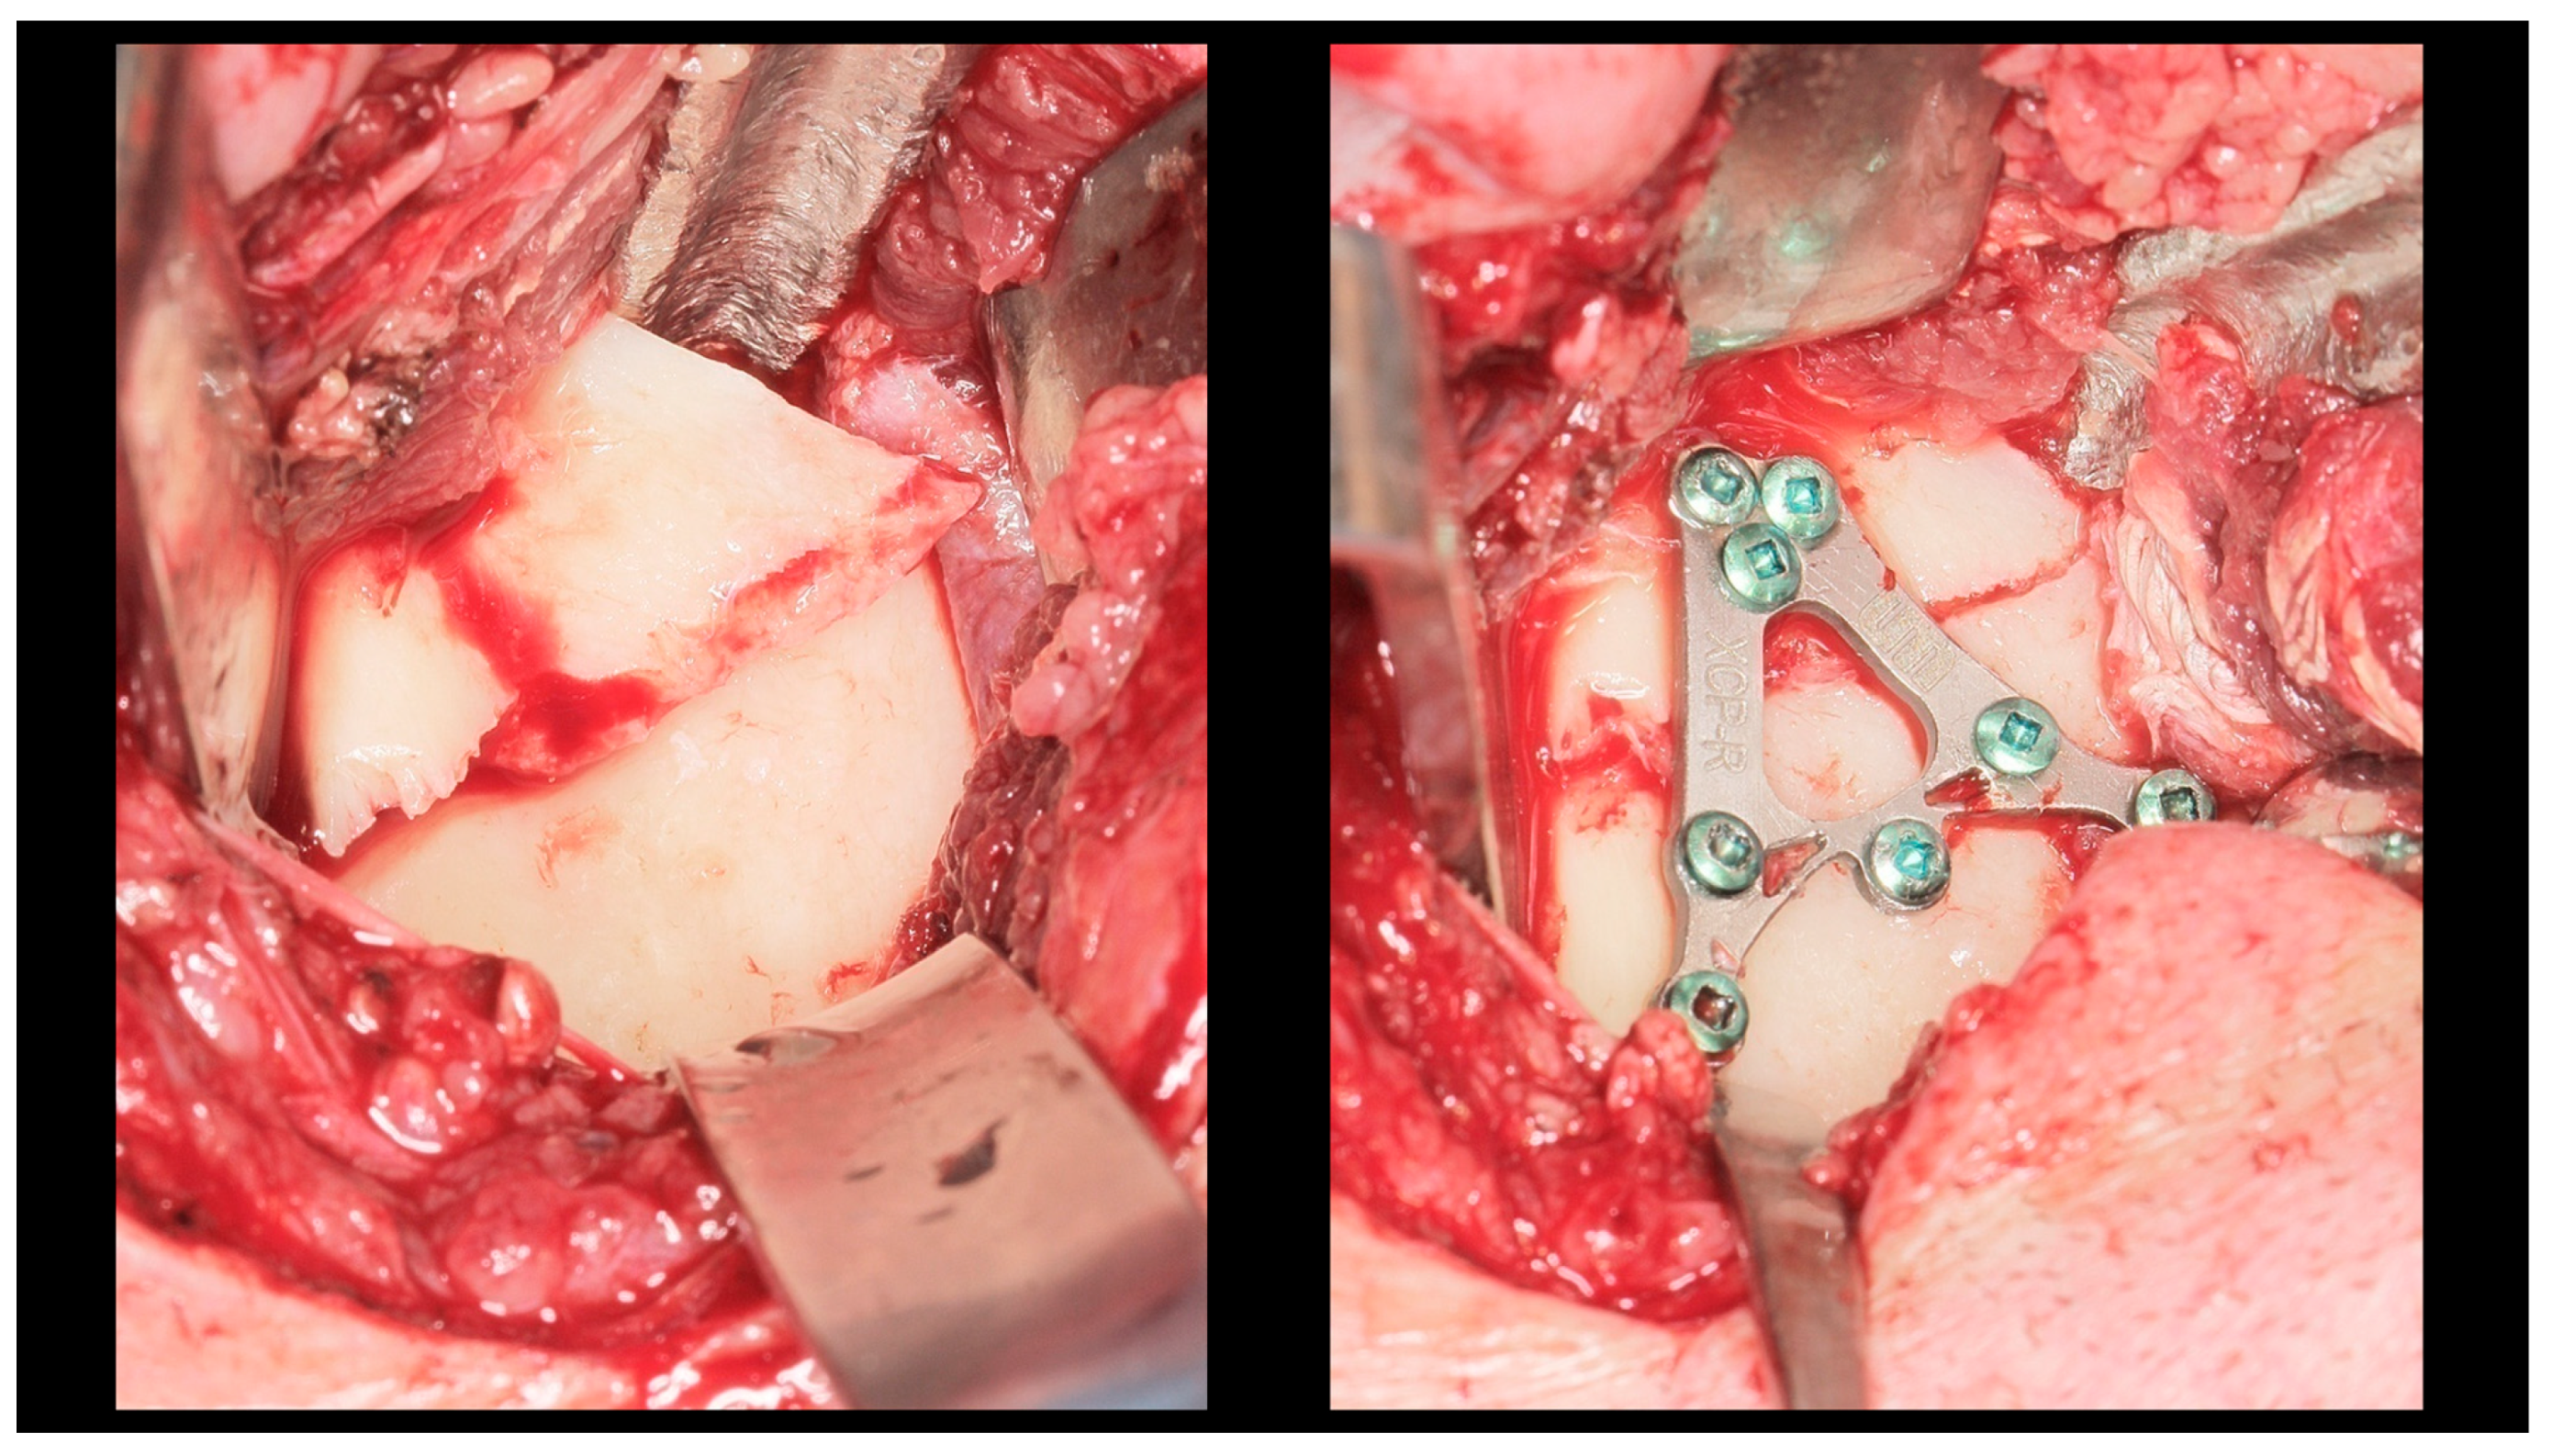

Figure 3.

Intra-operative view (retromandibular transparotid approach). The most commonly observed finding is lateral displacement with overlapping bone fragments (see left side). Osteosynthesis was performed using an XCP plate designed for fixation of the right side (see right side).

Figure 4.

Open rigid internal fixation was performed using a dedicated plate in the right condylar process (red arrow) and two straight plates of the 2.0 system on the left side of the mandibular body (yellow arrow).